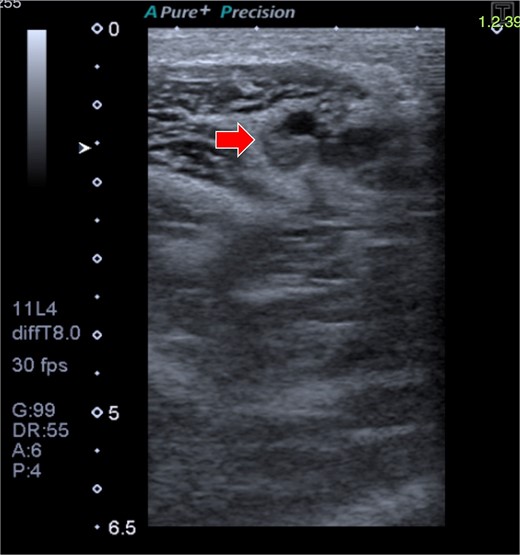

A 33-year-old woman with a history of oral contraceptive use and a BMI of 23.4 kg/m2 presented with breast hypoplasia. She was preoperatively evaluated and received an ASA I. A prepectoral augmentation mammoplasty was performed under general anesthesia. Même® MesmoMS® (Polytech Health & Aesthetics, Dieburg, Germany) 300-ml round implants were placed. The operative time was 80 minutes, and graduated compression stockings were used. On postoperative Day 7, the patient presented with pain, swelling, and erythema over the medial aspect of the right elbow and arm, with vital signs remaining normal. Doppler ultrasound revealed a right UEDVT (Fig. 2), and tomography showed thrombosis in the axillary and humeral veins (Fig. 3).

CT of the right upper extremity showing thrombosis of the right axillary and humeral veins (circle).